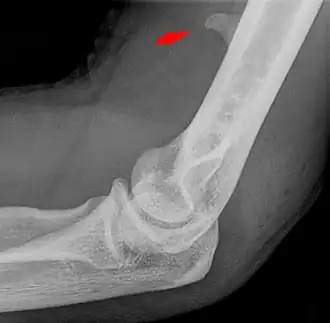

![]() Larger supracondylar process seen on a lateral radiograph of the elbow | |

The supracondylar process of the humerus (also known as an avian spur) is a variant bony projection on the anteromedial aspect of the upper arm bone (humerus), about 5–6 cm above the medial epicondyle.[1] It is directed downward, forward and medially pointing to the medial epicondyle. A fibrous band, Struthers ligament, may connect this process to the medial epicondyle.[2] This variation has a prevalence of 0.68% and is significantly more common in women than in men.[3]